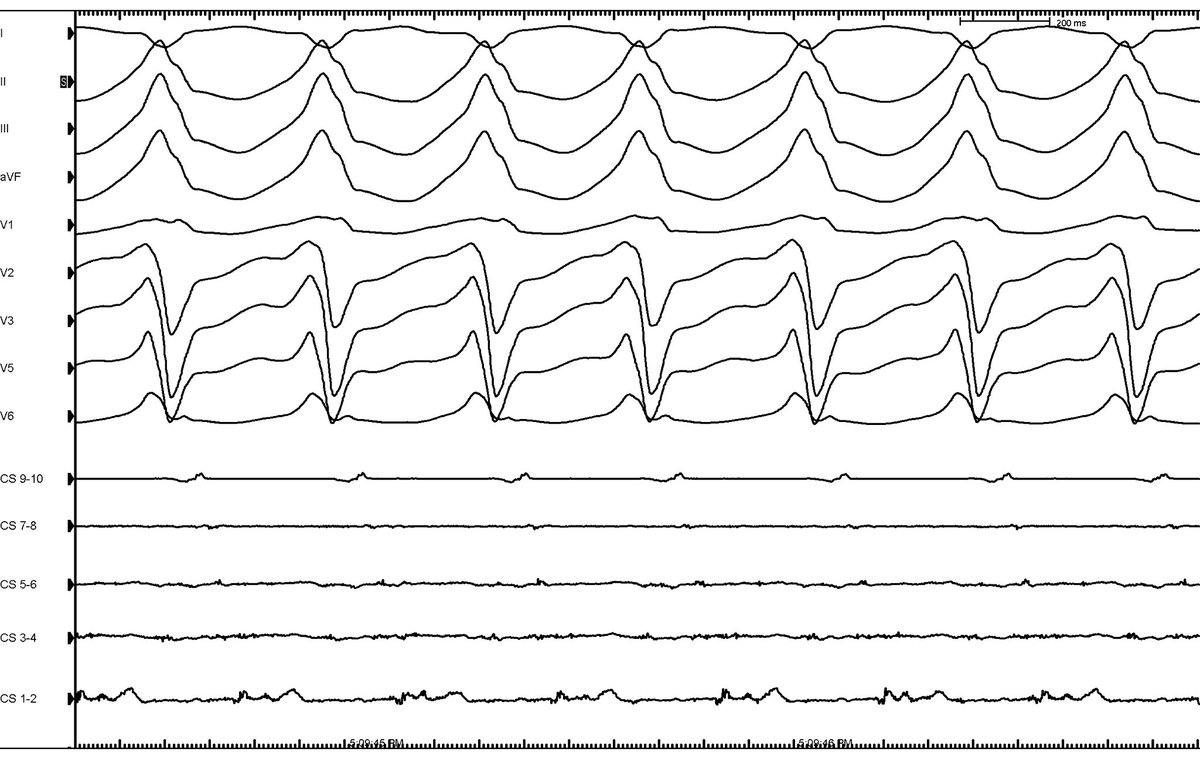

Wrapping up the academic year learning in depth VT mapping from @AMatthews0! @AbbottNews @MUSC_EP